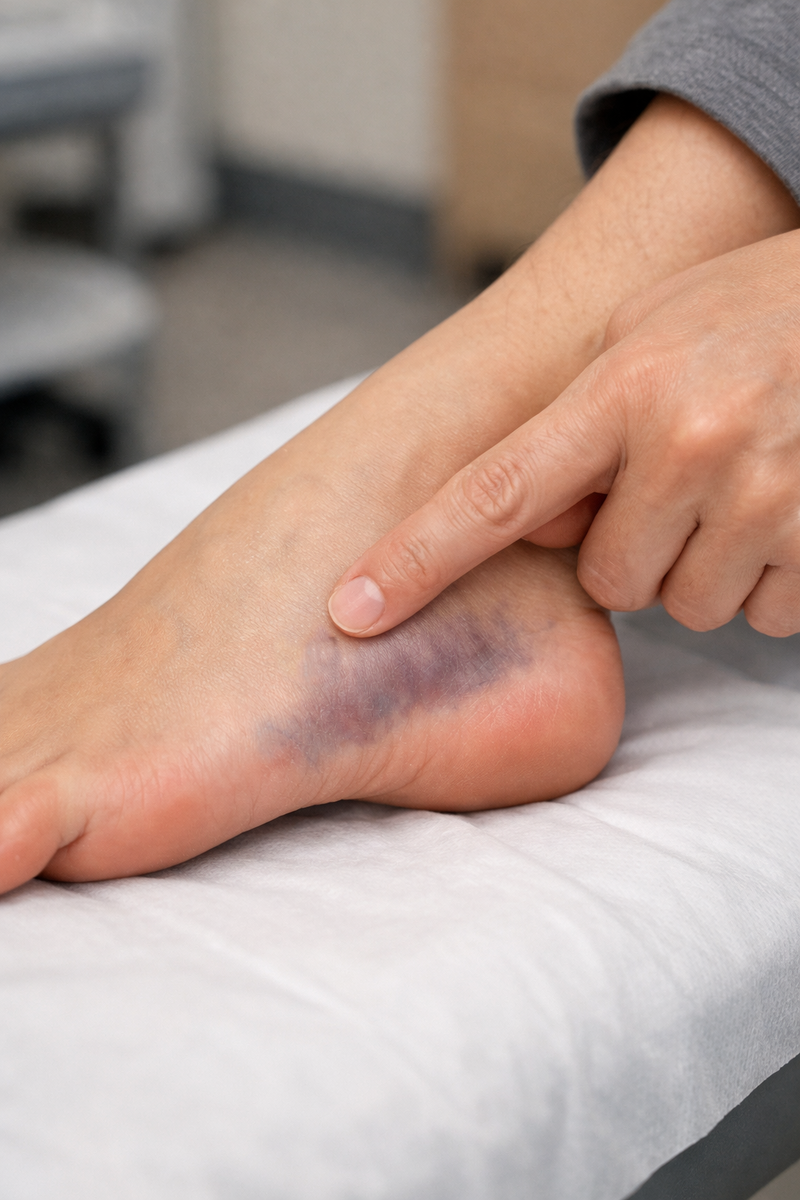

• резкая боль снаружи стопы после подворачивания/поворота;

• отек и синяк по наружному краю;

• боль усиливается при опоре и особенно при отталкивании;

• точечная болезненность при нажатии на основание 5-й плюсневой;

• ходьба “на пятке” возможна, но нормальная походка разваливается.